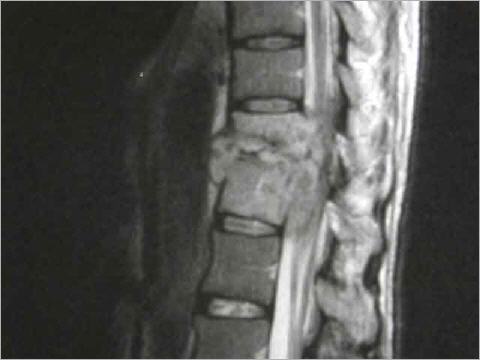

Mit Tuberkulose infizierter Wirbel: Bei Patienten mit schwachem Immunsystem kann die Wirbelsäule von Bakterien befallen werden.